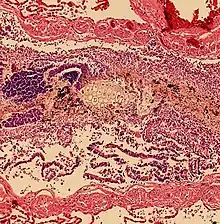

Pulmonary aspiration of acidic material (such as stomach acid) may produce an immediate primary injury caused by the chemical reaction of acid with lung parenchyma, and a later secondary injury as a result of the subsequent inflammatory response.[2]

Bacterial

Pulmonary aspiration may be followed by bacterial pneumonia. Community-acquired aspiration pneumonia is usually caused by anaerobic bacteria, whereas hospital-acquired aspiration pneumonia is more often caused by mixed flora, including both aerobic and anaerobic bacteria.[2]